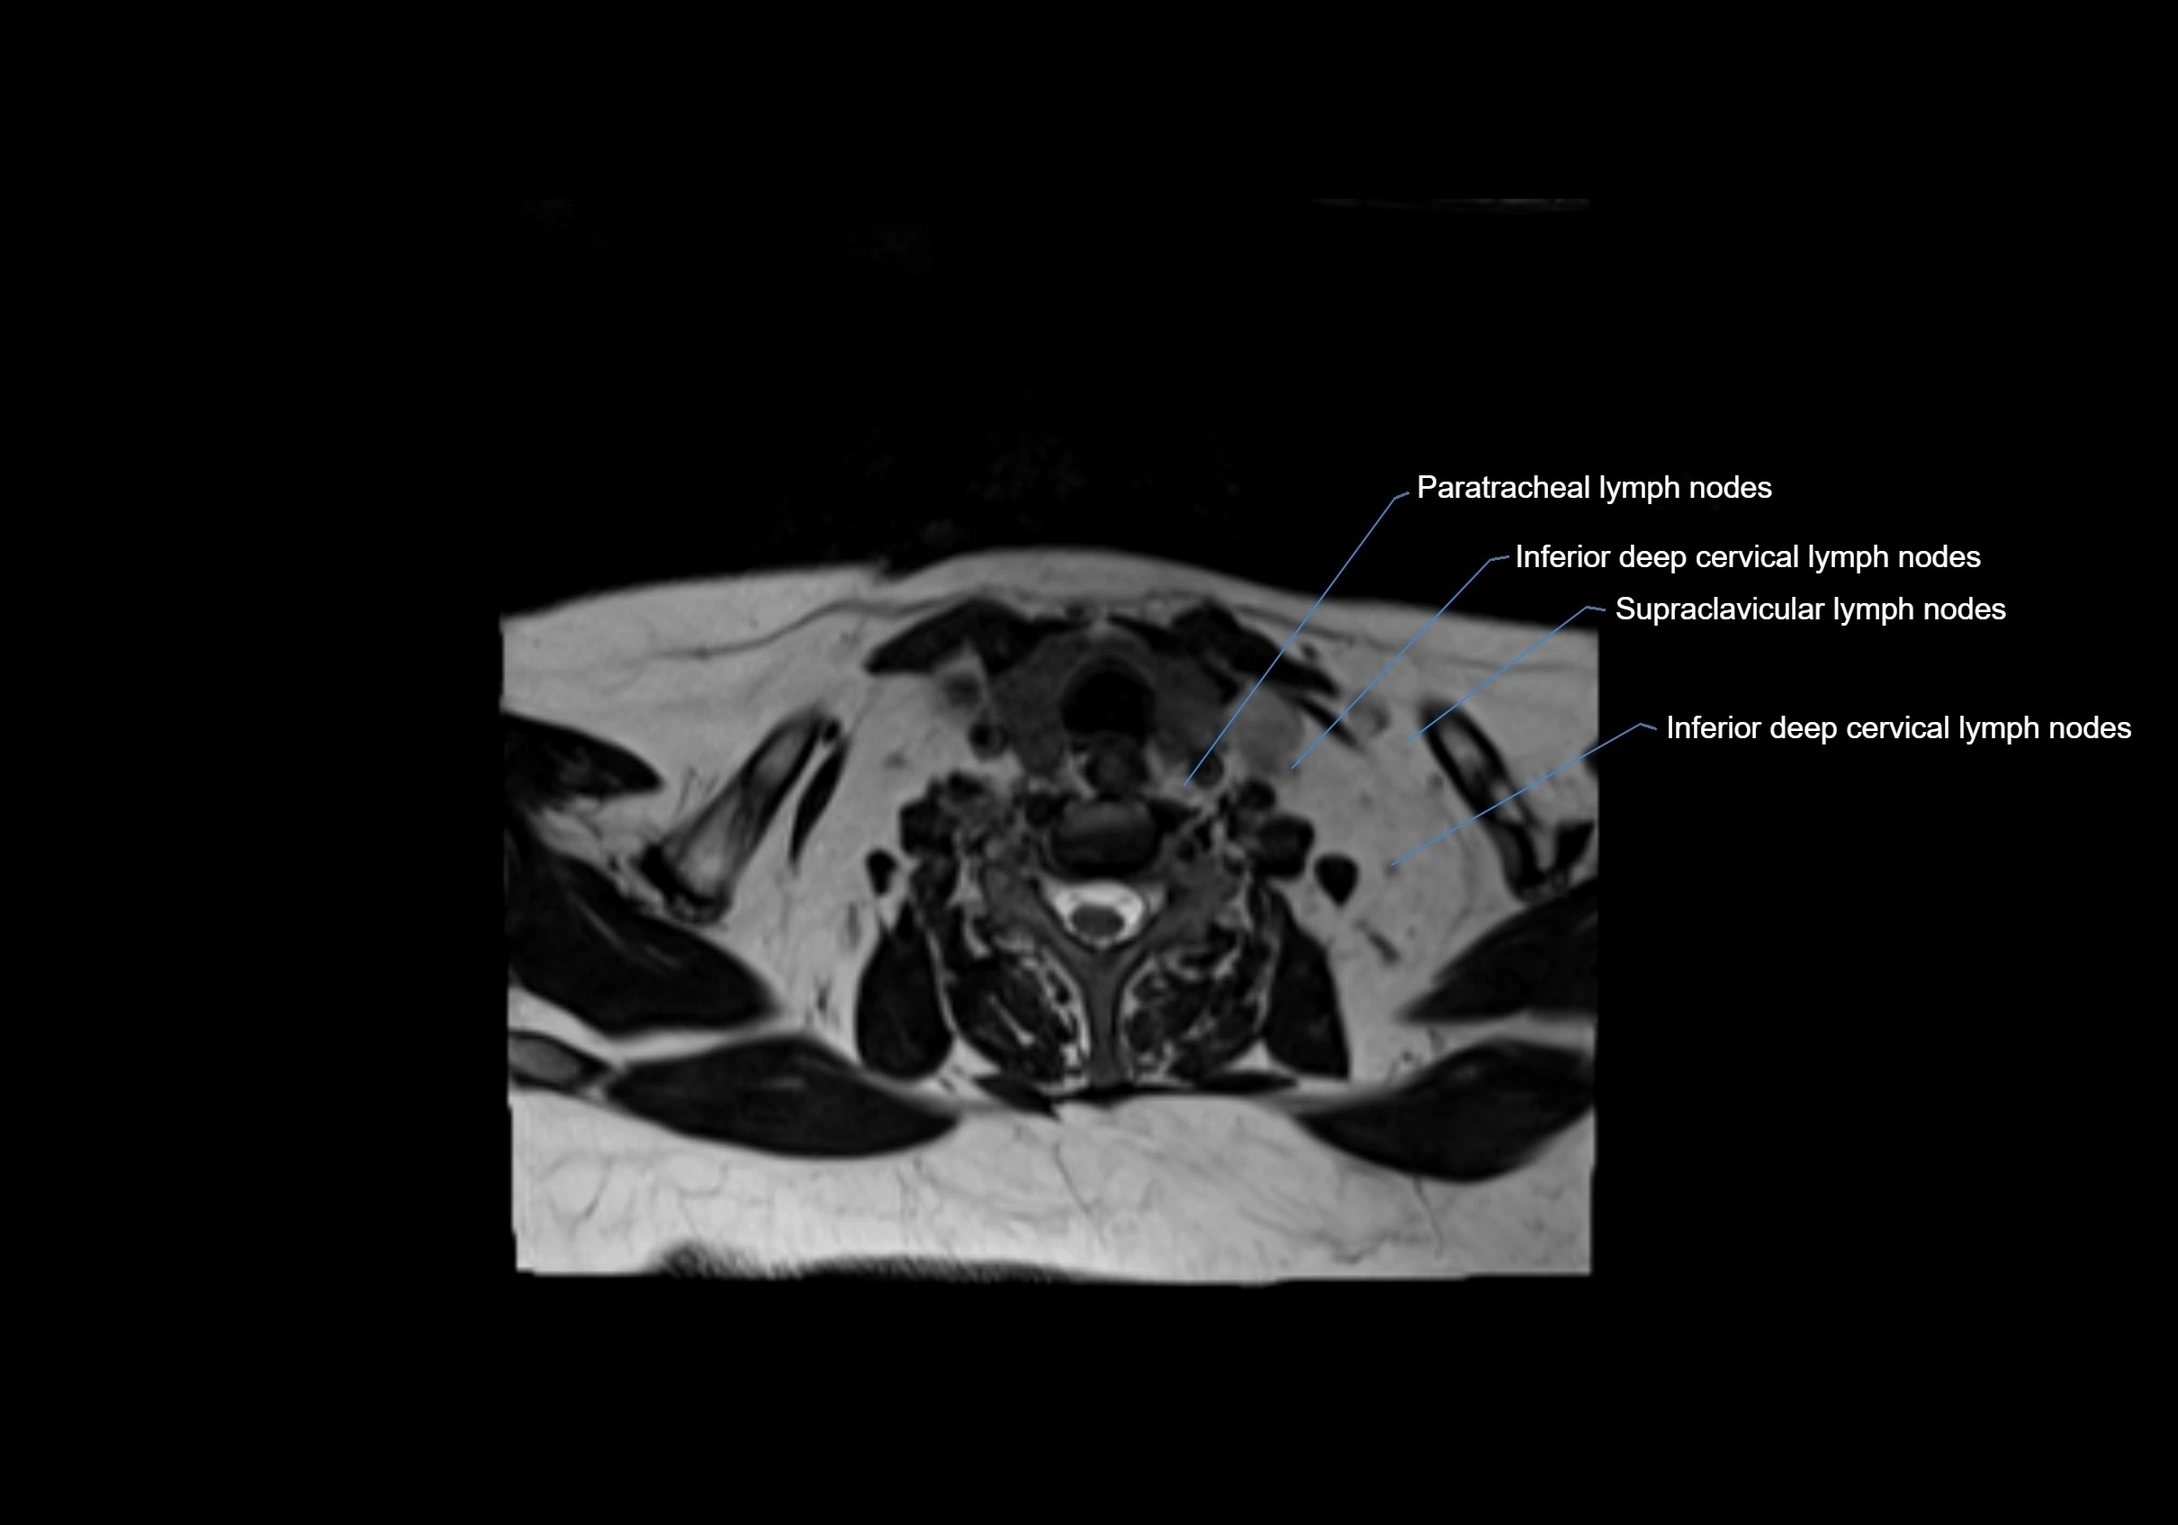

Location

• Found along primary lymph node chains, including preauricular, submandibular, parotid, and occipital regions

• Embedded in subcutaneous fat or superficial fascia, often lateral or posterior to primary nodes

• Variable in number; may occur unilaterally or bilaterally, depending on individual anatomy

MRI images

image